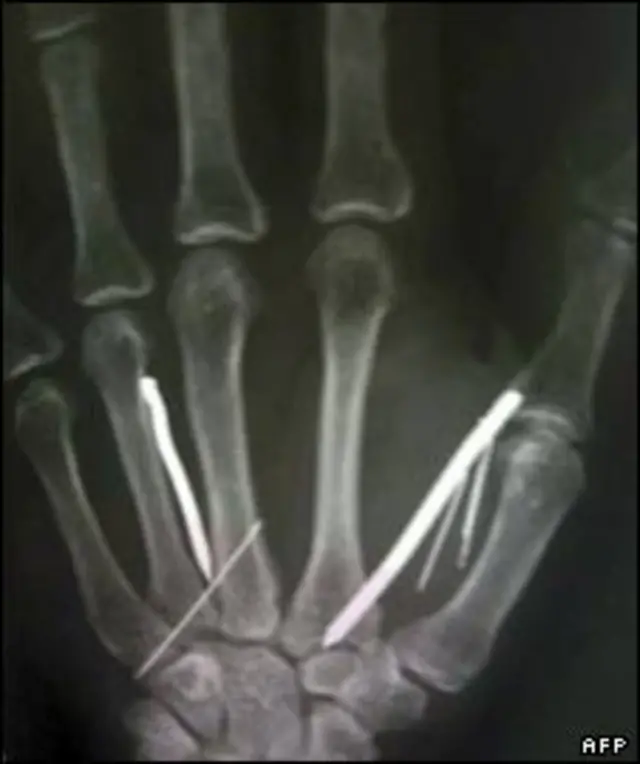

پزشکان گفته اند که شش سوزن را از دستهای این زن 49 ساله خارج نکرده اند چون نگران بوده اند به آنها صدمه وارد شود.

یکی از مسئولان بیمارستانی گفت طول میخ ها پنج سانتیمتر است. به گزارش خبرگزاری آسوشیتدپرس پزشک جراح گفته است که عمل جراحی با موفقیت بوده و زن مصدوم در راه بهبودی است.

پزشکان با عکسبرداری بیست و چهار سوزن و میخ در دستها و پاهای او یافته اند. او قادر نبود بنشیند یا به راحتی راه برود.